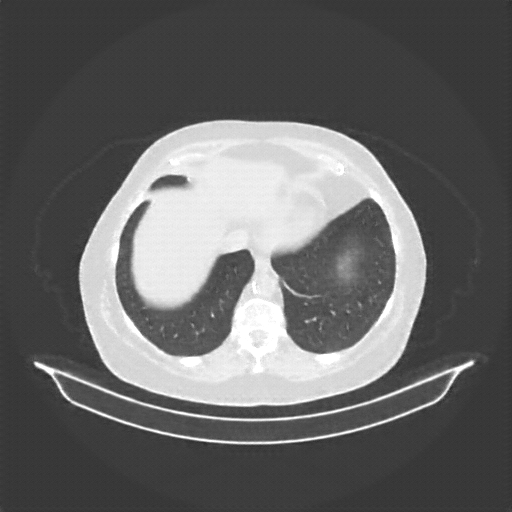

Slice 70 Targeting Evaluation

Slice: Slice_70

Slice Thickness: 3.0mm

Conversion: NATIVE β†’ VENOUS

Generated VENOUS CT scan (A→B translation)

No window - Raw intensity values